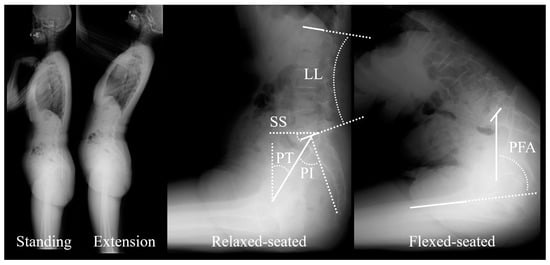

2.2. Data Collection and Radiographic Analysis